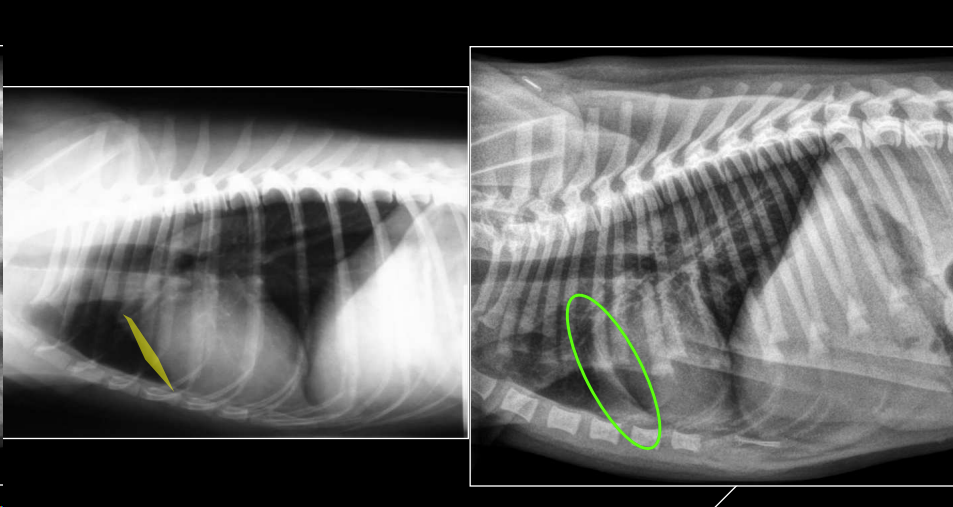

- Alteraciones de posición del mediastino (Desplazamiento mediastino VD)

- Alteraciones en la visualización de estructuras mediastinicas (Neumomediastino LL)

- Alteraciones de la anchura del mediastino (Derrame mediastinico o masa mediastinica VD)

2. Neumomediastino

- Aire en mediastino craneoventral.

- Mayor visualización de estructuras mediastínicas en vez de ver efecto masa en la zona mediastinica craneal, presencia de negros en la zona craneal y mejor visualización de vasos y traquea.

- “Tracheal stripe sign”.

- Puede coexistir con enfisema subcutáneo, neumotórax o neumoretroperitoneo.

- Generalmente por rotura traqueal (A veces por rotura esofágica)